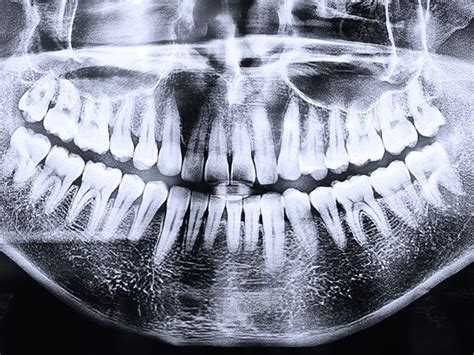

El diagnóstico radiológico es, junto con la exploración clínica, una prueba absolutamente esencial. En la mayoría de los casos, sobre todo en ausencia de una relación directa entre las raíces y el conducto dentario inferior, una ortopantomografía (OPG) y/o una radiografía intraoral serán suficientes para obtener la información necesaria.

De no conseguir información concluyente con estas imágenes se puede recurrir a técnicas de imagen tridimensionales como la tomografía volumétrica digital (TVD) o la tomografía computarizada (TC). Dado que no se ha demostrado un beneficio terapéutico claro con la obtención de imágenes tridimensionales preoperatorias se recomienda no incluir estos procedimientos de forma sistemática en los estudios diagnósticos.